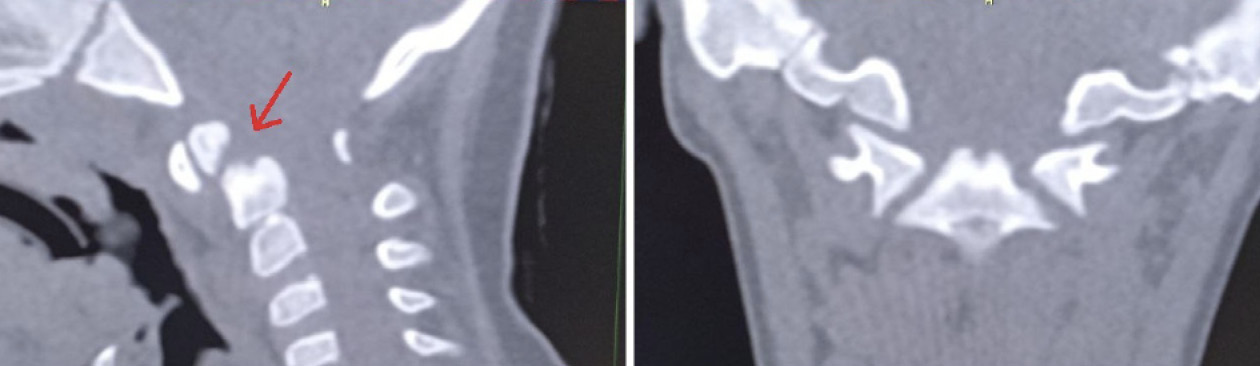

Было принято решение провести лечение в амбулаторных условиях, осуществляя устранение подвывиха с помощью бандажа для жесткой фиксации шейного отдела позвоночника, в виде постоянного ношения сроком на 7 дней. Кроме этого, был проведен курс лечебной гимнастики под контролем врача по лечебной физической культуре. По данным контрольного исследования КЛКТ, выполненной через 7 дней, отмечалась положительная динамика в виде уменьшения угла ротации атланта до 8° и восстановления конгруэнтности суставных поверхностей латерального атлантоаксиального сустава слева (рис. 4).

Рис. 4. Наложение изображений атланта и аксиса в аксиальной плоскости на контрольном исследовании после лечения

Пациентка Е. 9 лет обратилась на прием с жалобами на ограничение поворотов головой. Со слов матери, в мае 2018 г. ребенку проводилось оперативное лечение по поводу травмы шейного отдела позвоночника. Медицинские заключения не были предоставлены. При осмотре ребенок с синдромом Дауна. Голова по средней линии, пальпация области шейного отдела позвоночника безболезненна, объем пассивных и активных наклонов головы соответствовал нормативным значениям. При этом амплитуда пассивных и активных ротационных движений в шейном отделе позвоночника составила 15° и 20º в каждую сторону соответственно. При последующем ортопедическом осмотре было выявлено нарушение осанки по типу «сутулая спина» по Штаффелю. По данным анализа представленного диска с результатами ранее проведенной мультиспиральной компьютерной томографии шейного отдела позвоночника (дата исследования – май 2018 г.) был выявлен перелом зубовидного отростка С2 позвонка типа 1 по классификации L. D. Anderson и R.T. D'Alonzo, со смещением верхушки зубовидного отростка кпереди [9]. Плоскость перелома зубовидного отростка аксиса косая, края отломков неровные, нечеткие, диастаз между отломками неравномерный (рис. 5).

Рис. 5. Компьютерная томография шейного отдела позвоночника, сагиттальный срез (А), фронтальный срез на уровне зубовидного отростка С2 позвонка (Б). Стрелкой обозначено место перелома зубовидного отростка С2 позвонка